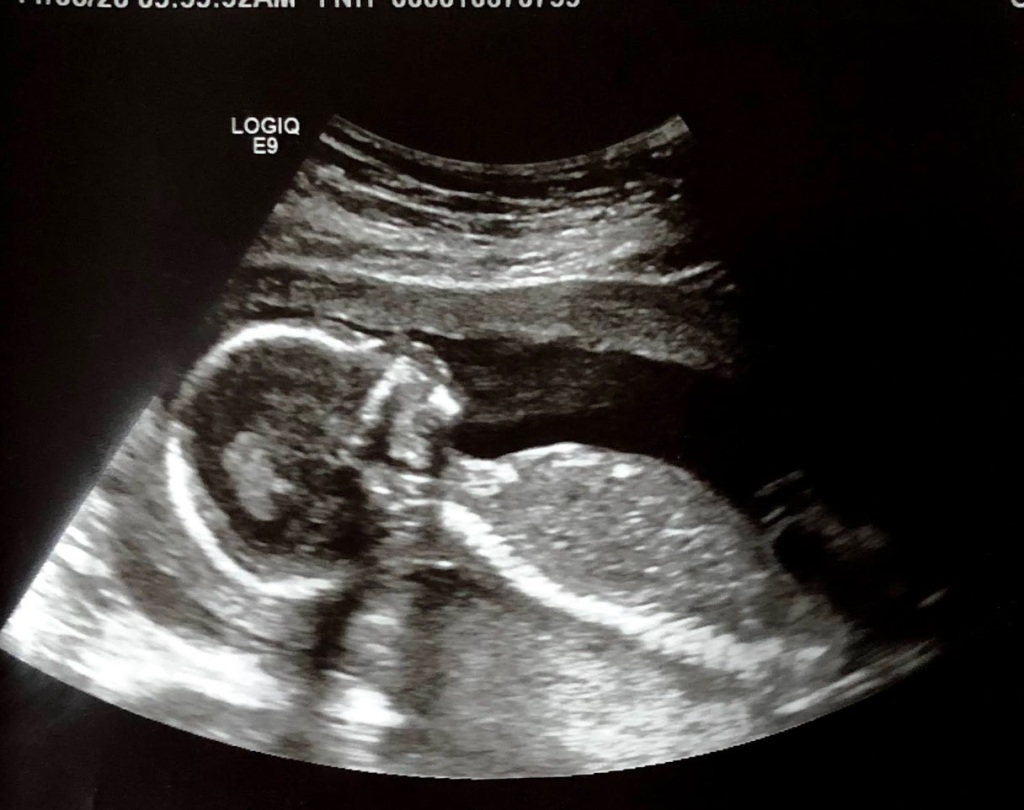

Ultrasound picture from November 2020.